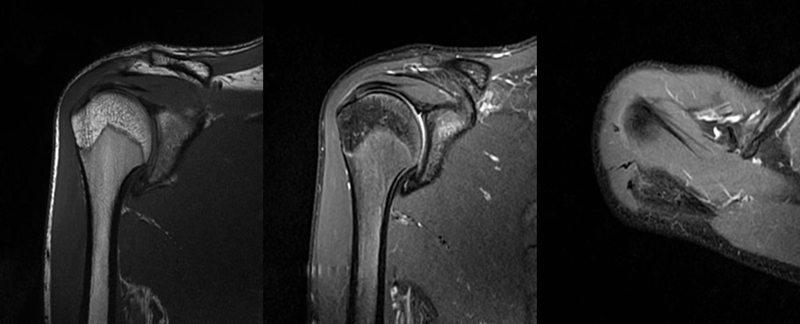

2、MRI检查

MRI目前是诊断肩袖疾病中最常用的检查,可以直观的观察肩袖肌腱。

图17 冈上肌

图18 冈下肌

图19 肩胛下肌

图20 小圆肌

图21 斜冠状位(临床常用)a.T2,b.T1

图22 斜矢状位 a.冈上肌出口,肩袖诊断不如斜冠状位;b.冈上肌及肌腹脂肪浸润成度,评估手术与否

图23 横断位a.正常肩胛下肌;b.肩胛下肌损伤

图24 a.肩袖全层撕裂;b.正常MRI

图25 巨大肩袖损伤(冈上肌)